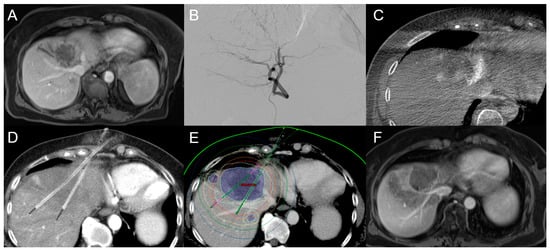

2.2.1. Computed Tomography High-Dose-Rate Brachytherapy (CT-HDRBT)

2.2.2. Irreversible Electroporation (IRE)